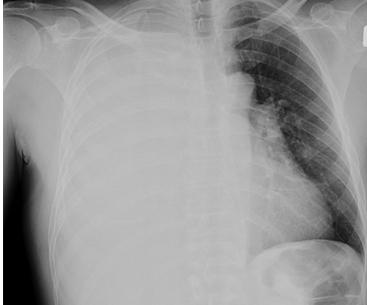

340) A 52 year old woman with history of triple-negative, metastatic breast cancer presents to the Emergency Room with increasing shortness of breath. This is her third Emergency room visit in the past 2 months. Earlier, she was admitted to the hospital twice for massive pleural effusion and underwent therapeutic thoracentesis. She was told that the cancer had spread to her lungs and pleura. She received multiple courses of chemotherapy in the past and her cancer has progressed despite initial response to chemotherapy. Her oncologist recommended palliative care. On examination, she is afebrile, respiratory rate is 24/min, Blood pressure 120/70 mm Hg and Heart Rate 106/min. Breath sounds are decreased on right side of the chest. D-dimer level is 60ng/ml ( normal < 500 ng/ml) . A chest X-ray is shown below:

Which of the following management options is most appropriate for this patient?

A) Obtain Pleural biopsy

B) Tube thoracostomy and Pleurodesis

C) Start Heparin and obtain CT Angiogram

D) Pleuro-perintoneal shunt

E) Repeat Therapeutic thoracentesis

Filed under: Uncategorized, USMLE Test Prep | Tagged: Archer cardiology, Archer oncology, archer palliative care, Archer pulmonology, Archer radiology, USMLE STEP 3 CARDIOLOGY, USMLE STEP 3 ONCOLOGY, usmle step 3 palliative care, USMLE STEP 3 PULMONOLOGY, USMLE STEP 3 RADIOLOGY | 17 Comments »